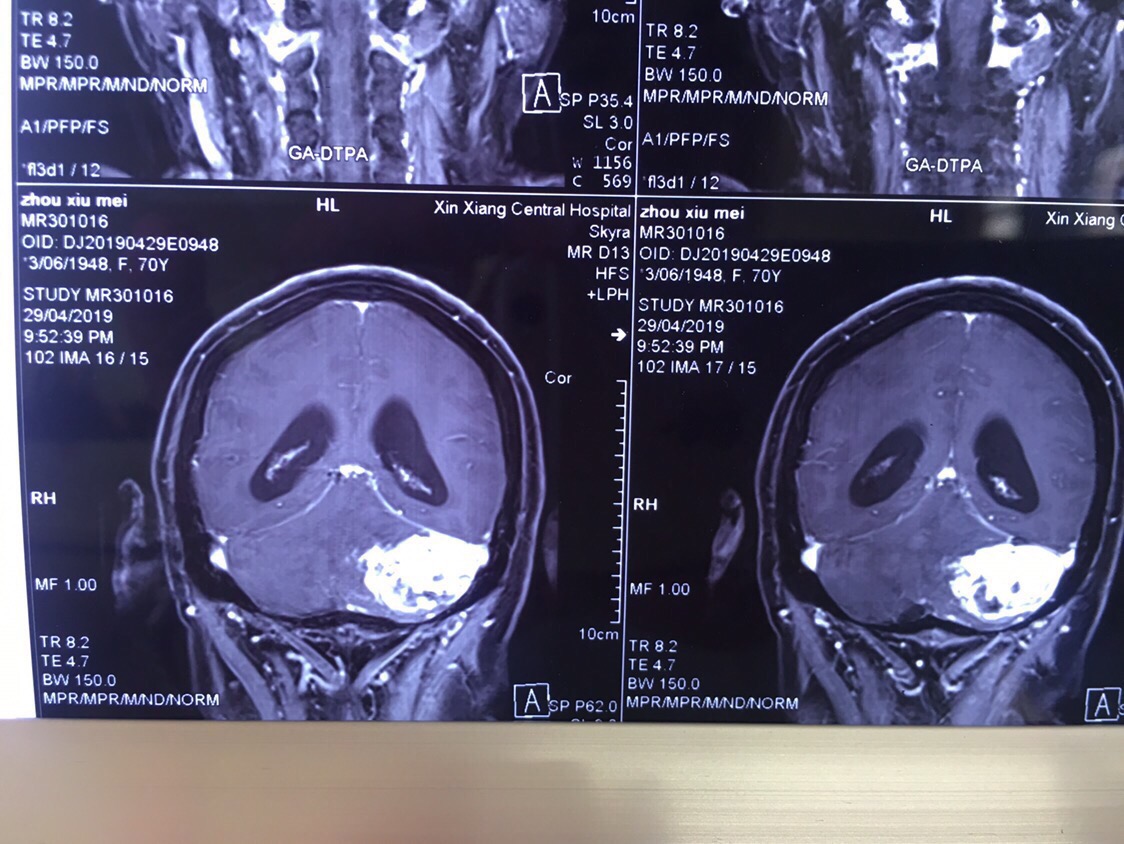

患者周某,女,70岁,以“间断头痛伴恶心呕吐五天”为主诉入院。既往患有高血压病3年,糖尿病3年,冠心病2年,控制情况一般。查体:神志模糊,精神差,可对答,回答正确,能完成简单指令性动作,反应迟钝,双瞳孔等大等圆,直径约3mm,光反射灵敏。指鼻试验不准,轮替试验缓慢。跟膝胫试验不稳。病理反射未引出。诊断:1.左侧小脑实性血管母细胞瘤,2.梗阻性脑积水,3.高血压病,4.冠心病,5.2型糖尿病。

增强冠位